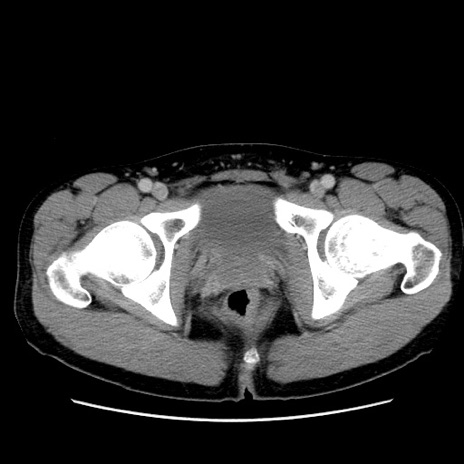

症例36(横断像)

【症例】20歳代 男性

【主訴】心窩部痛

【現病歴】今朝より上腹部痛あり。一旦軽快していたが再度出現したため救急要請。昨日夕に白身の魚を含む刺身を食べた。

【身体所見】BP 136/89mmHg、HR 74/min、BT 37.0℃、腹部:膨満、軟、心窩部に圧痛あり。反跳痛なし、筋性防御なし、腸雑音やや亢進あり。

【データ】WBC 17700、CRP 0.48